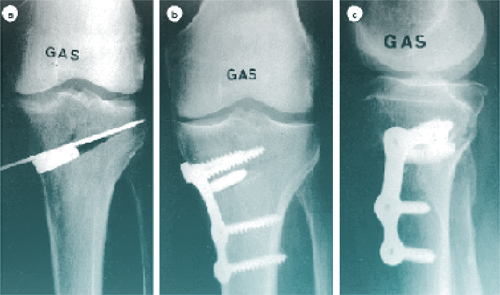

L’intervention dure environ une heure. Je réalise une coupure partielle du tibia (ostéotomie) pour l’ouvrir et redresser l’axe. Cette ouverture est maintenue par une plaque vissée et comblée par un substitut osseux ou une greffe.